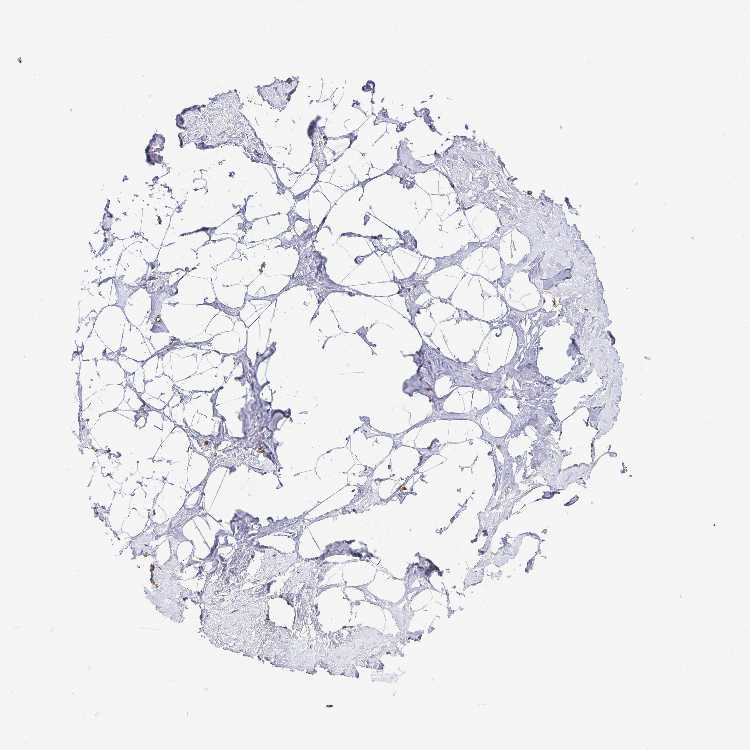

Breast

BREAST - Expression summary

Protein expression

Breasti

On the top, protein expression in current human tissue, based on all annotated cell types, is reported with the units not detected (n), low (l), medium (m) and high (h). Underneath, protein expression in each annotated cell type are reported using the same units.

Protein expression data is based on knowledge-based annotation. For genes where more than one antibody has been used, a collective score is set.

If knowledge-based annotation could not be performed for a gene, no data is displayed here. View antibody staining data further down this page.

Adipocytes: Not detected

Glandular cells: Medium

Myoepithelial cells: Medium

BREAST - Antibody stainingi

Antibody staining in the annotated cell types in the current human tissue is reported as not detected, low, medium, or high, based on conventional immunohistochemistry profiling in selected tissues. This score is based on the combination of the staining intensity and fraction of stained cells.

Each image is clickable and will lead to virtual microscopy that enables deeper exploration of all samples and also displays staining intensity scores, fraction scores and subcellular localization as well as patient and tissue information for each sample.

Antibody HPA037890

Adipocytes Not detected

Glandular cells Medium

Myoepithelial cells Medium